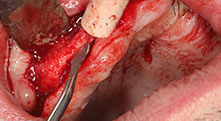

Pr Bratu : Nous préférons prélever l'os sur la crête oblique externe de la mandibule postérieure, et non dans la région interforaminale. Après l'incision des tissus mous, nous utilisons les nouvelles scies pour définir la quantité d'os à prélever. De la même manière, nous les utilisons également pour la totalité de la préparation dans presque 80 % des cas. Nous avons également parfois recours à d'autres instruments piézoélectriques et, pour terminer, à un burin pour mobiliser le bloc. Nous trouvons cette technique chirurgicale très efficace.

Pr Bratu : Nous avons volontiers recours à la technique sandwich pour les augmentations mandibulaires latérales. La préparation d'un couvercle osseux est réalisée à l'aide de la scie piézoélectrique et le fragment crestal est fixé à l'aide de microvis. Nous plaçons un mélange de matériau de substitution osseuse autologue et xénogénique entre les deux. Cela fonctionne très bien. Il faut toujours s'assurer que les coupes verticales aient des dimensions suffisantes lors du clivage de la crête alvéolaire dans la mandibule. Sinon, l'os risque de se casser facilement.

Pr Bratu : J'estime que la chirurgie piézoélectrique a fait faire un grand bon en avant à la chirurgie orale. Grâce à cette technique, la préparation osseuse est plus sûre et plus facile. Par exemple, les extractions entraînent une perte osseuse minime. C'est très important d'un point de vue esthétique, surtout si la pose d'implants est prévue immédiatement.

La chirurgie piézo est également plus sûre pour les tissus mous. Ainsi, les dommages causés aux membranes dans le sinus ont pratiquement disparu, de même que les atteintes nerveuses lors du prélèvement des blocs osseux. On dispose également de données indiquant une diminution des gonflements et des douleurs postopératoires. La chirurgie piézoélectrique convient idéalement à la préparation des septa sinusiens. Et dernier avantage, mais pas le moindre, nos patients apprécient le caractère atraumatique de cette technologie.